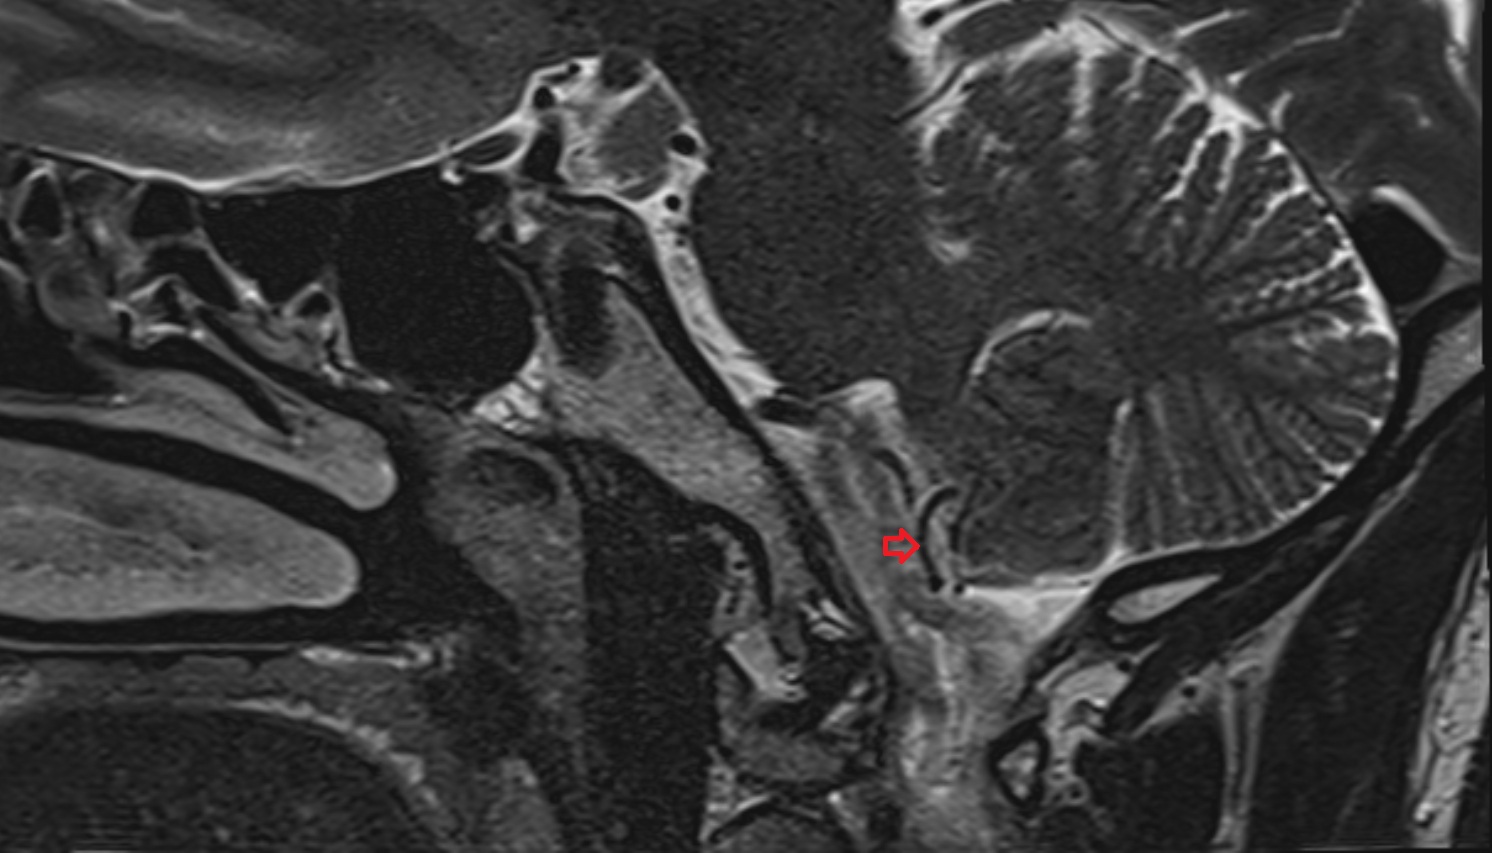

- Traversing nerve root of spinal nerve

- Exiting nerve root of spinal nerve